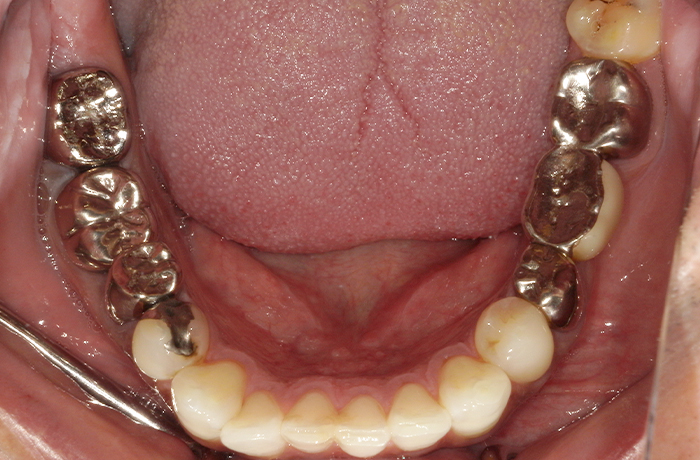

治療前

口腔内写真とレントゲン写真

右上2番は骨吸収が進み、動揺と咬合痛を伴っていました。

保存困難な状態であり、審美的にも歯頚ライン(歯の見えている部分と歯肉や顎骨に埋まっている部分の境界)の不調和が見られました。